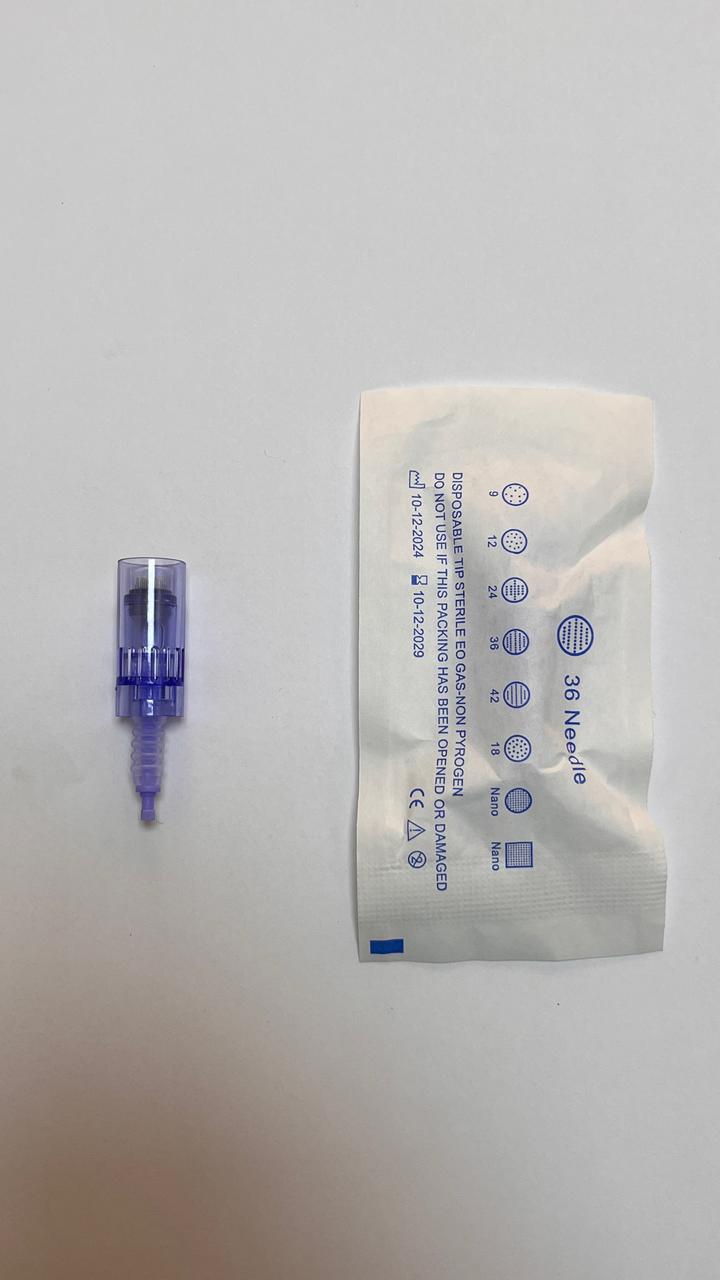

DERMA PEN CARTRIDGE

DERMA PEN CARTRIDGE